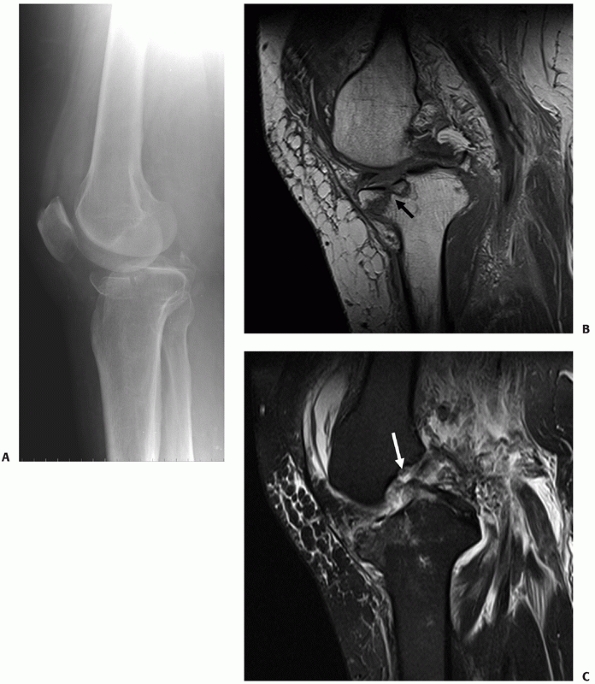

degree of articular displacement and also identifies occult fracture

MRI provides additional information about injuries to the soft tissue

modalities (Fig. 53-7). However, whether MRI

whether it should be used instead of CT scanning is controversial. CT

scans better visualize the fracture anatomy than do MR images but MRI

demonstrates associated soft tissue injuries, particularly those of the

menisci and ligaments, that are not visualized on CT. When tibial

plateau fractures were assessed with both techniques, CT was found to

be sensitive and specific in identifying ligament injuries because most

of them had at least small bony avulsions, but MRI was necessary to

detect meniscal injuries.121

![]() |

FIGURE 53-7 A. Lateral radiograph shows an unusual anterior fracture subluxation (AO/OTA type B3). B. Sagittal MR images show the fracture (black arrow) and (C) the torn posterior collateral ligament (white arrow).